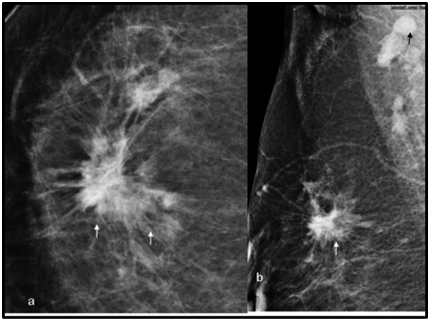

The patient was referred for mammogram, which showed right breast well-defined dense lesion with speculated margins measuring 3.7 x 3.0 cm highly suspicious for malignancy. In addition the rounded dense axillary lymph nodes on the right side (Figure 3A&B). Her surgical oncology clinical examination 4 months after the biopsy revealed a palpable right breast mass measuring 7 x 6cm, mobile, not attached to skin or chest wall. The histopathology of her right breast mass showed invasive lobular carcinoma grade1, LVI was positive, Estrogen Receptor (ER) strongly positive > 80%. Progesterone Receptor (PR) strongly positive > 90%. Her-2 was negative with Ki67 of 10%. Surprisingly another smaller breast mass was found in the contralateral breast for which biopsy was performed and the result was invasive lobular carcinoma grade 1 with ER strongly positive in 80%, PR moderately positive in 10% and Her-2 negative.

Figure 3 Cranio-caudal. (A) Medio-lateral. (B) mammogram views of the right breast showing a multifocal infiltrative whiskery lobular carcinoma (white arrows) with a rounded dense mass representing an involved axillary lymph node (black arrow).